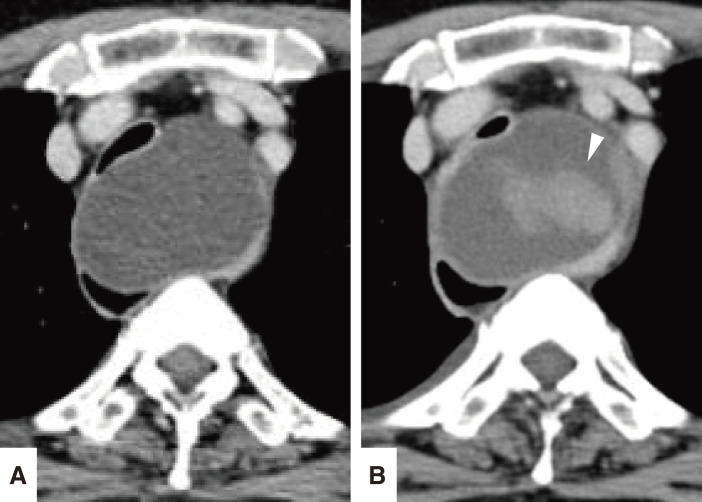

Case presentation: A 64-year-old woman with exertional dyspnea was diagnosed with a superior mediastinal cyst compressing the trachea and esophagus. Preoperative EUS-FNA was performed to reduce the cyst volume and any mitigate potential complications during anesthesia induction. Three days later, she developed dyspnea due to a delayed intracystic hemorrhage, necessitating emergency surgery. VATS with a confronting upside-down monitor setup was performed under standby V-A ECMO. Despite a limited surgical field under 2-lung ventilation, a confronting upside-down VATS approach allowed sufficient visualization and maneuverability. The patient had an uneventful recovery, with no recurrence at 3 months.